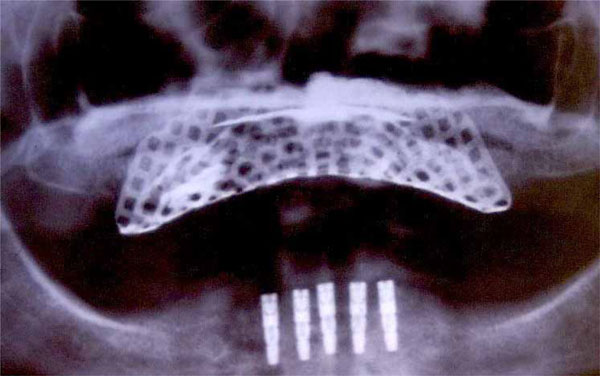

Before surgery, partially edentulous patients received proper oral hygiene instructions and oral hygiene treatment. At the end of the initial therapy, before starting the surgical procedures, the patients demonstrated proper plaque control. All patients underwent radiographic exams prior to surgery (Figs. 1 and 2).

Fig. (1).

Pre-operative orthopantomograph.